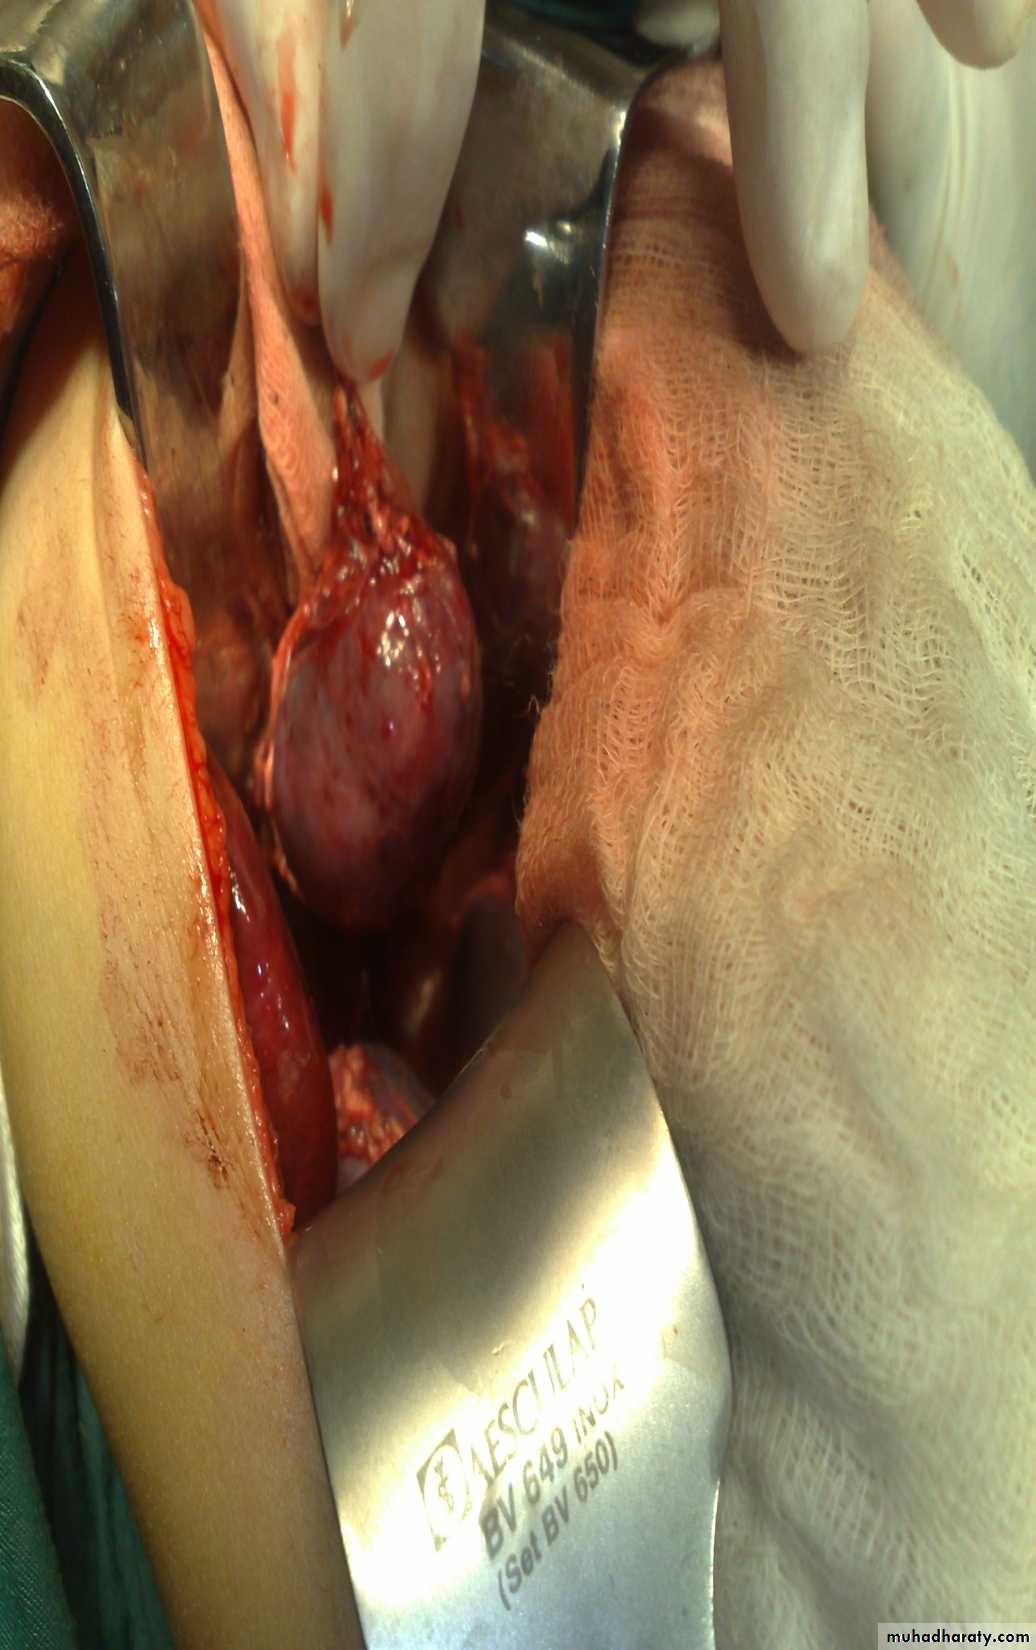

Abdominal Wall Defects